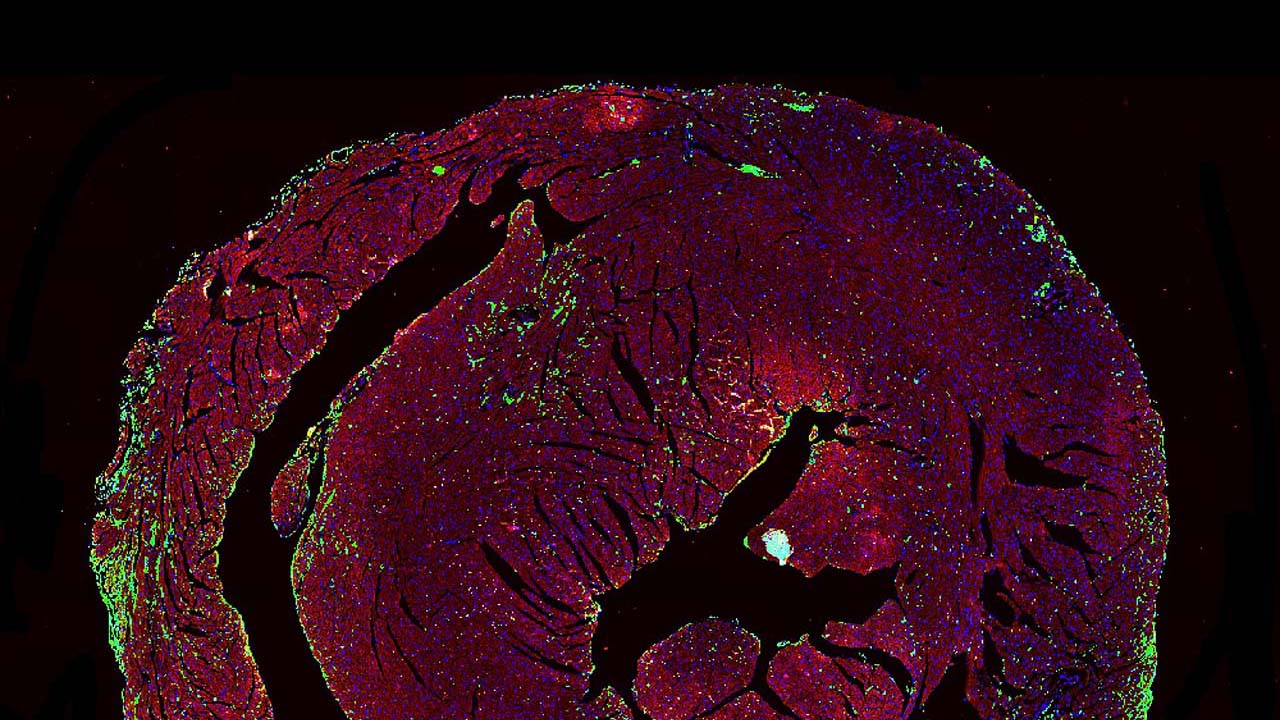

Microscopy of a mouse heart with immune infiltrates indicating ICI-myocarditis.

Microscopy of a mouse heart with immune infiltrates indicating ICI-myocarditis. Photo by UCSF